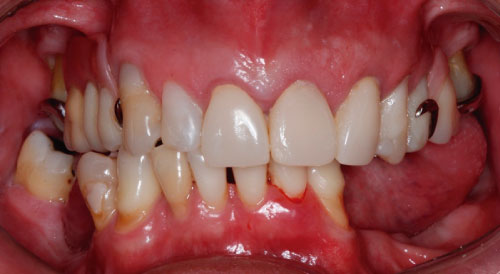

A 52-year-old man presented at the Oral Implant Dentistry Department of the Faculty Ilapeo, Curitiba, Brazil. The same complained of generalized mobility in the lower teeth. At the first moment, anamnesis and radiographic examination were performed. At the time of the clinical and radiographic examination was noted the presence of periodontal disease with points of exacerbation, generalized bone loss and mobility grade 2 in teeth (Figure 1 and Figure 2). It was suggested the extraction of the inferior dental elements for placement of dental implants and installation of a denture about implants with immediate loading.

Figure 1: Clinical image showing the initial oral condition of the patient. View Figure 1